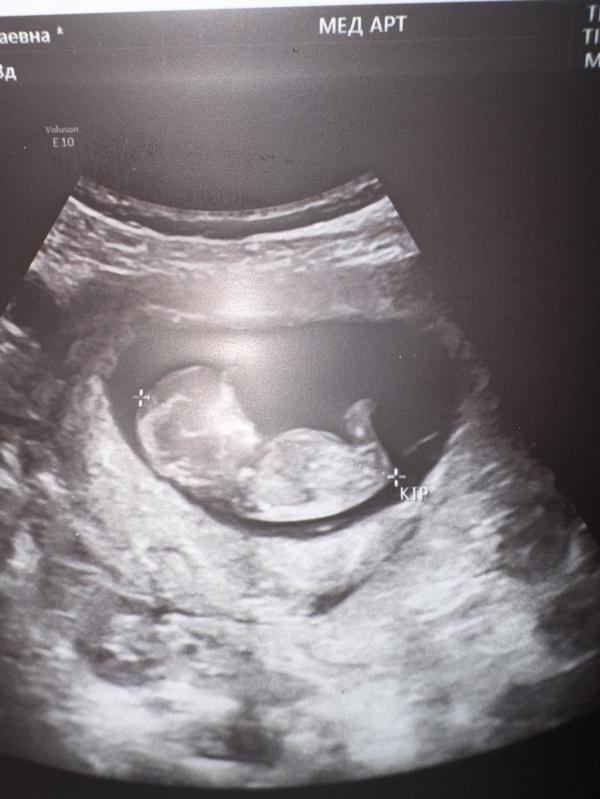

Кто родится, мальчик или девочка? УЗИ показало 11 и 3 недели беременности, пол малыша

Как думаете мальчик или девочка ? 11и 3 нед

@rukiyat.abdullayeva.97, бугорок прямой

У моей дочки точно такое узи было

Ну если конечно ничего не вырастет там 😂

А пока похожа на девочку

Не видно же👀

Не вижу половой бугорок